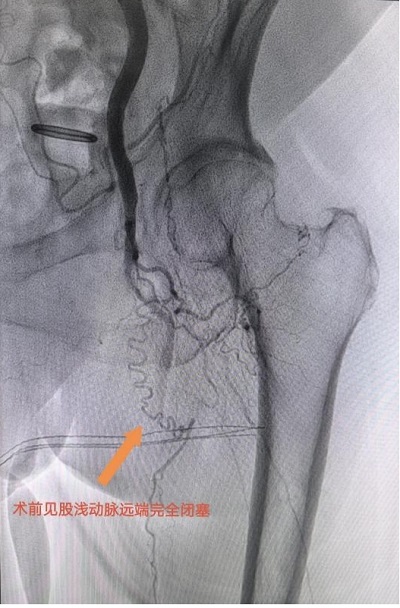

“結(jié)合病史和體征,我們高度懷疑下肢動脈硬化閉塞癥?!碧撇┱{(diào)出影像檢查報告,果然如他所想,結(jié)果顯示李曉蕓左側(cè)股淺動脈至腘動脈完全閉塞,血管遠(yuǎn)端僅存一根頭發(fā)絲粗細(xì)的供血通道,動脈壁鈣化嚴(yán)重且布滿血栓,宛如一段廢棄的枯河。

患者左腿動脈血管閉塞嚴(yán)重。重醫(yī)附屬大學(xué)城醫(yī)院供圖

“這是典型的下肢動脈硬化閉塞癥晚期?!碧撇┙忉尩?。由于患者病變范圍從大腿根部蔓延至腳趾,動脈硬化程度嚴(yán)重到無法通過影像精準(zhǔn)定位,加上82歲高齡及較差的肺功能,無法耐受全身麻醉,如要進(jìn)行手術(shù)則風(fēng)險極高。